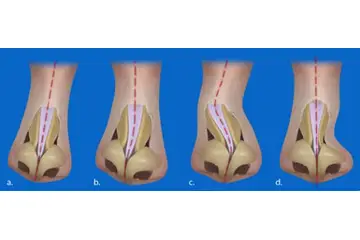

Kıkırdak Doku Çeşitleri Kıkırdak doku, bağ dokuları arasında yer alan, esnek ve dayanıklı bir yapıya sahip olan dokulardır. Farklı türleri ve işlevleri, vücudun çeşitli bölgelerinde önemli roller üstlenmektedir. Bu makalede, kıkırdak dokunun çeşitleri ve özellikleri detaylı bir şekilde ele alınacaktır. Kıkırdak Doku Türleri Kıkırdak doku üç ana türde sınıflandırılmaktadır: hyalin kıkırdak, elastik kıkırdak ve fibröz kıkırdak. Her bir tür, farklı yapısal özelliklere ve işlevsel amaçlara sahiptir.

Kıkırdak Dokunun Özellikleri Kıkırdak dokunun bazı ayırt edici özellikleri şunlardır:

Kıkırdak Doku ve Hastalıklar Kıkırdak dokunun sağlık durumu, birçok hastalığın gelişiminde önemli bir rol oynamaktadır. Osteoartrit gibi dejeneratif hastalıklar, kıkırdak dokusunun bozulmasıyla ilişkilidir. Ayrıca, kıkırdak dokunun yaralanmaları, spor yaralanmaları ve travmalar sonucunda meydana gelebilmektedir. Kıkırdak Doku Araştırmaları ve Gelecek Perspektifleri Günümüzde kıkırdak doku araştırmaları, doku mühendisliği ve yenileyici tıp alanında yoğunlaşmaktadır. Kıkırdak hasarını onarmak veya yeniden oluşturmak amacıyla hücresel tedavi yöntemleri ve biyomühendislik uygulamaları geliştirilmektedir. Bu alandaki ilerlemeler, kıkırdak ile ilgili hastalıkların tedavisinde önemli yenilikler getirebilir. Sonuç olarak, kıkırdak doku, vücutta önemli bir rol oynamakta olup, farklı türleriyle birlikte çeşitli işlevler üstlenmektedir. Bu yapıların sağlığı, genel sağlık durumu üzerinde önemli bir etkiye sahiptir ve araştırmalar bu alanda devam etmektedir. |